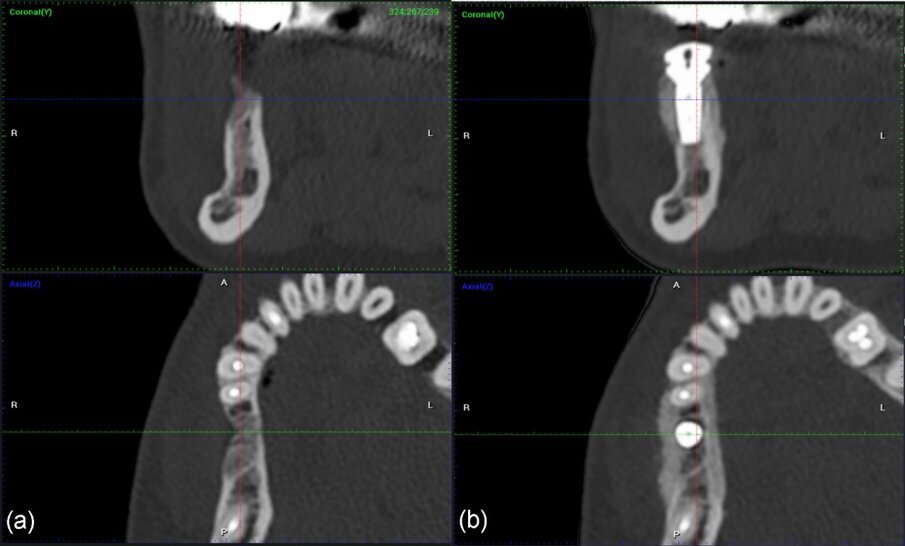

Ri-valutazione radiologica

Le immagini CBCT sono state ottenute utilizzando un sistema di radiografia computerizzata CS8100 3D Carestream (Carestream Health) con una dimensione di voxel di 0,150 mm e un campo visivo di 8x9 cm prima (T1) e 16 settimane (T2) dopo l’inserimento dell’impianto. I file originali in formato DICOM sono stati importati nel software Romexis (Planmeca) per l’analisi. Per entrambi i set di dati T1 e T2, abbiamo selezionato per la valutazione delle sezioni trasversali nel mezzo del sito sulla sezione assiale e perpendicolare alla cresta alveolare (Fig. 25).

Fig. 25_a), b): Immagini coronali e assiali CBCT prima dell’intervento chirurgico e a 4 mesi dopo l’intervento.

Rivalutazione radiologica

La stessa metodologia del caso 1 è stata applicata per il confronto T1-T2-T3. La valutazione è stata effettuata attraverso sezioni trasversali prese nel mezzo del sito sulla sezione assiale e perpendicolari alla cresta alveolare (Figg. 28, 29).

Fig. 29_Valutazione CBCT del caso 2 da sinistra a destra: a) immagini coronali e assiali preoperatorie; b) immagini coronali e assiali CBCT post-operatorie a 4 mesi; c) immagini coronali e assiali CBCT a 2 anni e 7 mesi.